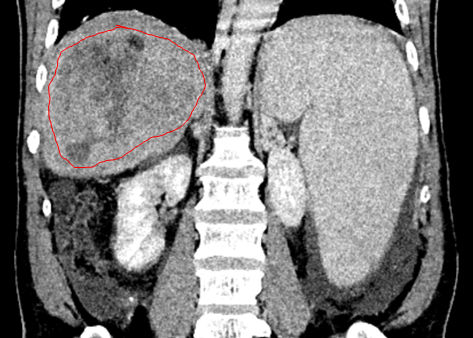

一位 60 岁的男性患者因反复解黑便 25 天来院就诊,全腹部 CT 平扫加增强检查结果令人揪心:肝右叶多发占位,大者范围约 110 mm×70 mm,考虑原发性肝癌,伴门脉右支及主干癌栓可能;同时还发现肝硬化,脾大,食管胃底静脉曲张,门静脉高压伴侧支循环开放,腹盆腔积液。追溯病史发现,早在 2019 年,该患者就已通过 CT 检查确诊肝硬化、脾大及门静脉高压伴侧支循环开放,但 6 年间未进行任何定期复查,最终错失了早期干预的机会。

图 3:冠状位示边界不清的肝右叶巨大肝癌(红色圈)